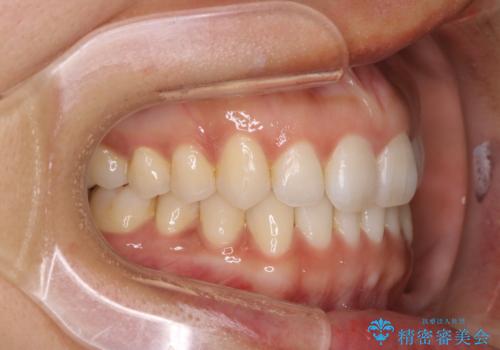

【インビザライン】前歯をきれいな歯並びにしたい

- 前歯の叢生を主訴に来院されました。このケースは抜歯をせずにIPRにてスペースを確保し、並べる計画をたてました。

きちんと使用時間を守って使用していただいたことで短い期間で治療が終了しました。